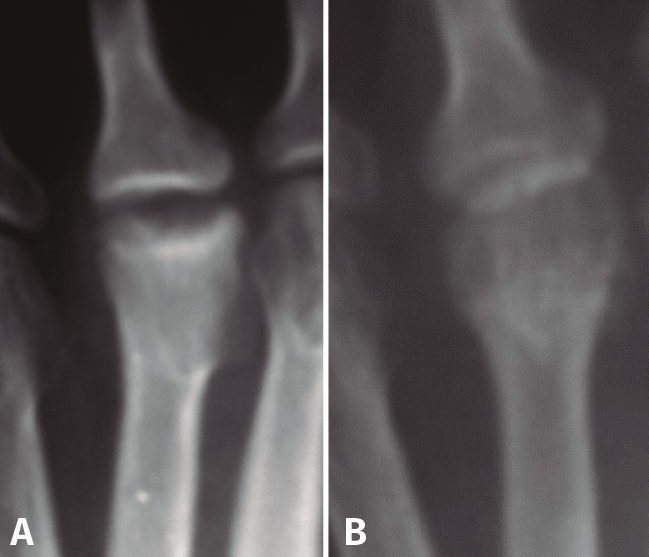

Figura 4. Estadios de Smillie. A: estadio I; B: estadio II; C: estadio III; D: estadio IV; E: estadio V.

Basándose en la historia natural de la enfermedad y atendiendo a los cambios radiológicos, Smillie(16) clasifica, con propósito terapéutico, la lesión en 5 estadios (Figura 4):

- Estadio 1: aparece una línea de fractura a través de la epífisis.

- Estadio 2: se produce una depresión central de la cabeza por colapso del hueso subcondral. El espacio articular puede ensancharse.

- Estadio 3: la depresión central hace que se proyecten hacia delante los bordes medial y lateral de la cabeza, manteniéndose intacta la parte plantar.

- Estadio 4: la parte central necrosada de la cabeza puede desprenderse de la parte plantar, formándose un cuerpo libre articular.

- Estadio 5: aplanamiento de la cabeza metatarsal y van apareciendo los cambios degenerativos secundarios.